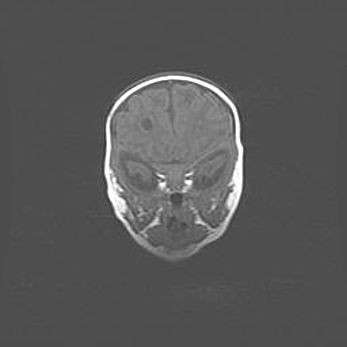

Церебральная ишемия II.

Возраст: 5 дней

Вес: 3400 г

Пол: женский

Окружность головы: 35 см

Срок гестации: 39 недель

Церебральная ишемия – это заболевание, характеризующееся недостаточностью (гипоксией) либо полным прекращением (аноксией) снабжения мозга кислородом по причине закупорки одного или нескольких сосудов. Это приводит к  что метаболическим расстройствам различной степени тяжести в тканях головного мозга, развитию коагуляционных некрозов и гибели нейронов.